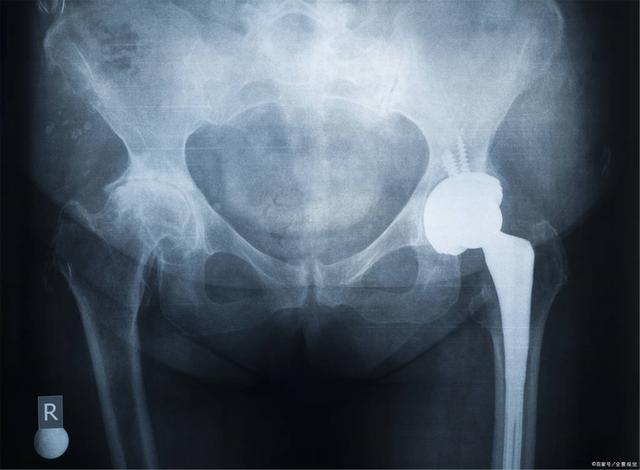

“通过仔细询问病史、查体并分析影像学资料后,初步诊断吴冰为髋关节滑膜骨软骨瘤病。” 滕学仁告诉记者,吴冰关节内游离体就像“老鼠”一样四处窜动,需要手术取出。

“吴冰的情况比较罕见,髋关节里滑膜组织过度增生,形成较多滑膜组织的硬结,导致髋关节里的游离体很多。” 滕学仁表示,该病病因目前尚未明确,滑膜骨软骨瘤病多发于中青年人,滑膜因反应性化生形成软骨结节,后期软骨结节可发生钙化或骨化。此病好发于关节,尤以膝、髋、肘、肩关节多见,掌指和指间关节滑囊及腱鞘偶有发生,多为单侧发病。

“滑膜骨软骨瘤病发生于髋关节者少见,且髋关节部位深,极容易误诊。” 滕学仁告诉记者,此前通过微创关节镜技术取出膝、肘、肩关节游离体案例较多,吴冰髋关节内游离体多,取出难度大。

“髋关节内游离体多,需要开三个不到一厘米的小口,用关节镜穿到关节腔周围;髋关节部位深,关节镜需要穿入20厘米左右,抓取游离体难度大。”术前, 滕学仁针对吴冰的情况认真分析了手术的重难点。

滕主任仔细清理患侧髋关节,寻找游离的软骨,经过3小时10分钟手术,最终为吴冰取出了81枚游离体,成功解除了患者病痛。

手术后,吴冰复查CT,显示她的髋关节内游离体清理得非常干净,由于手术只有3个不足1厘米的微小切口。